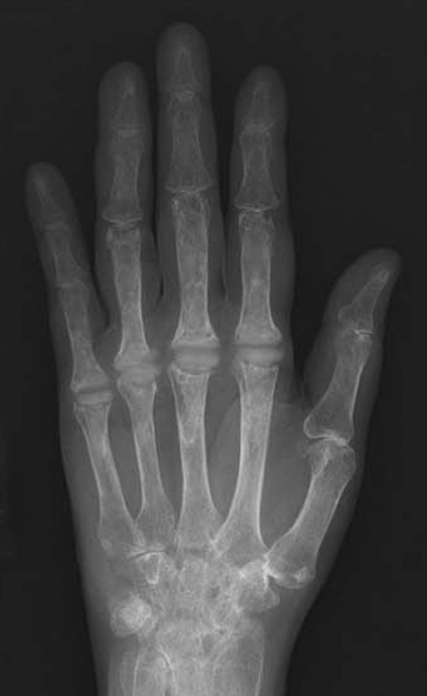

X-ray showing MCP joint replacement with silicone implants

X-ray of a patient who has had the MCP joints of their index through pinky fingers replaced with silicone implants.